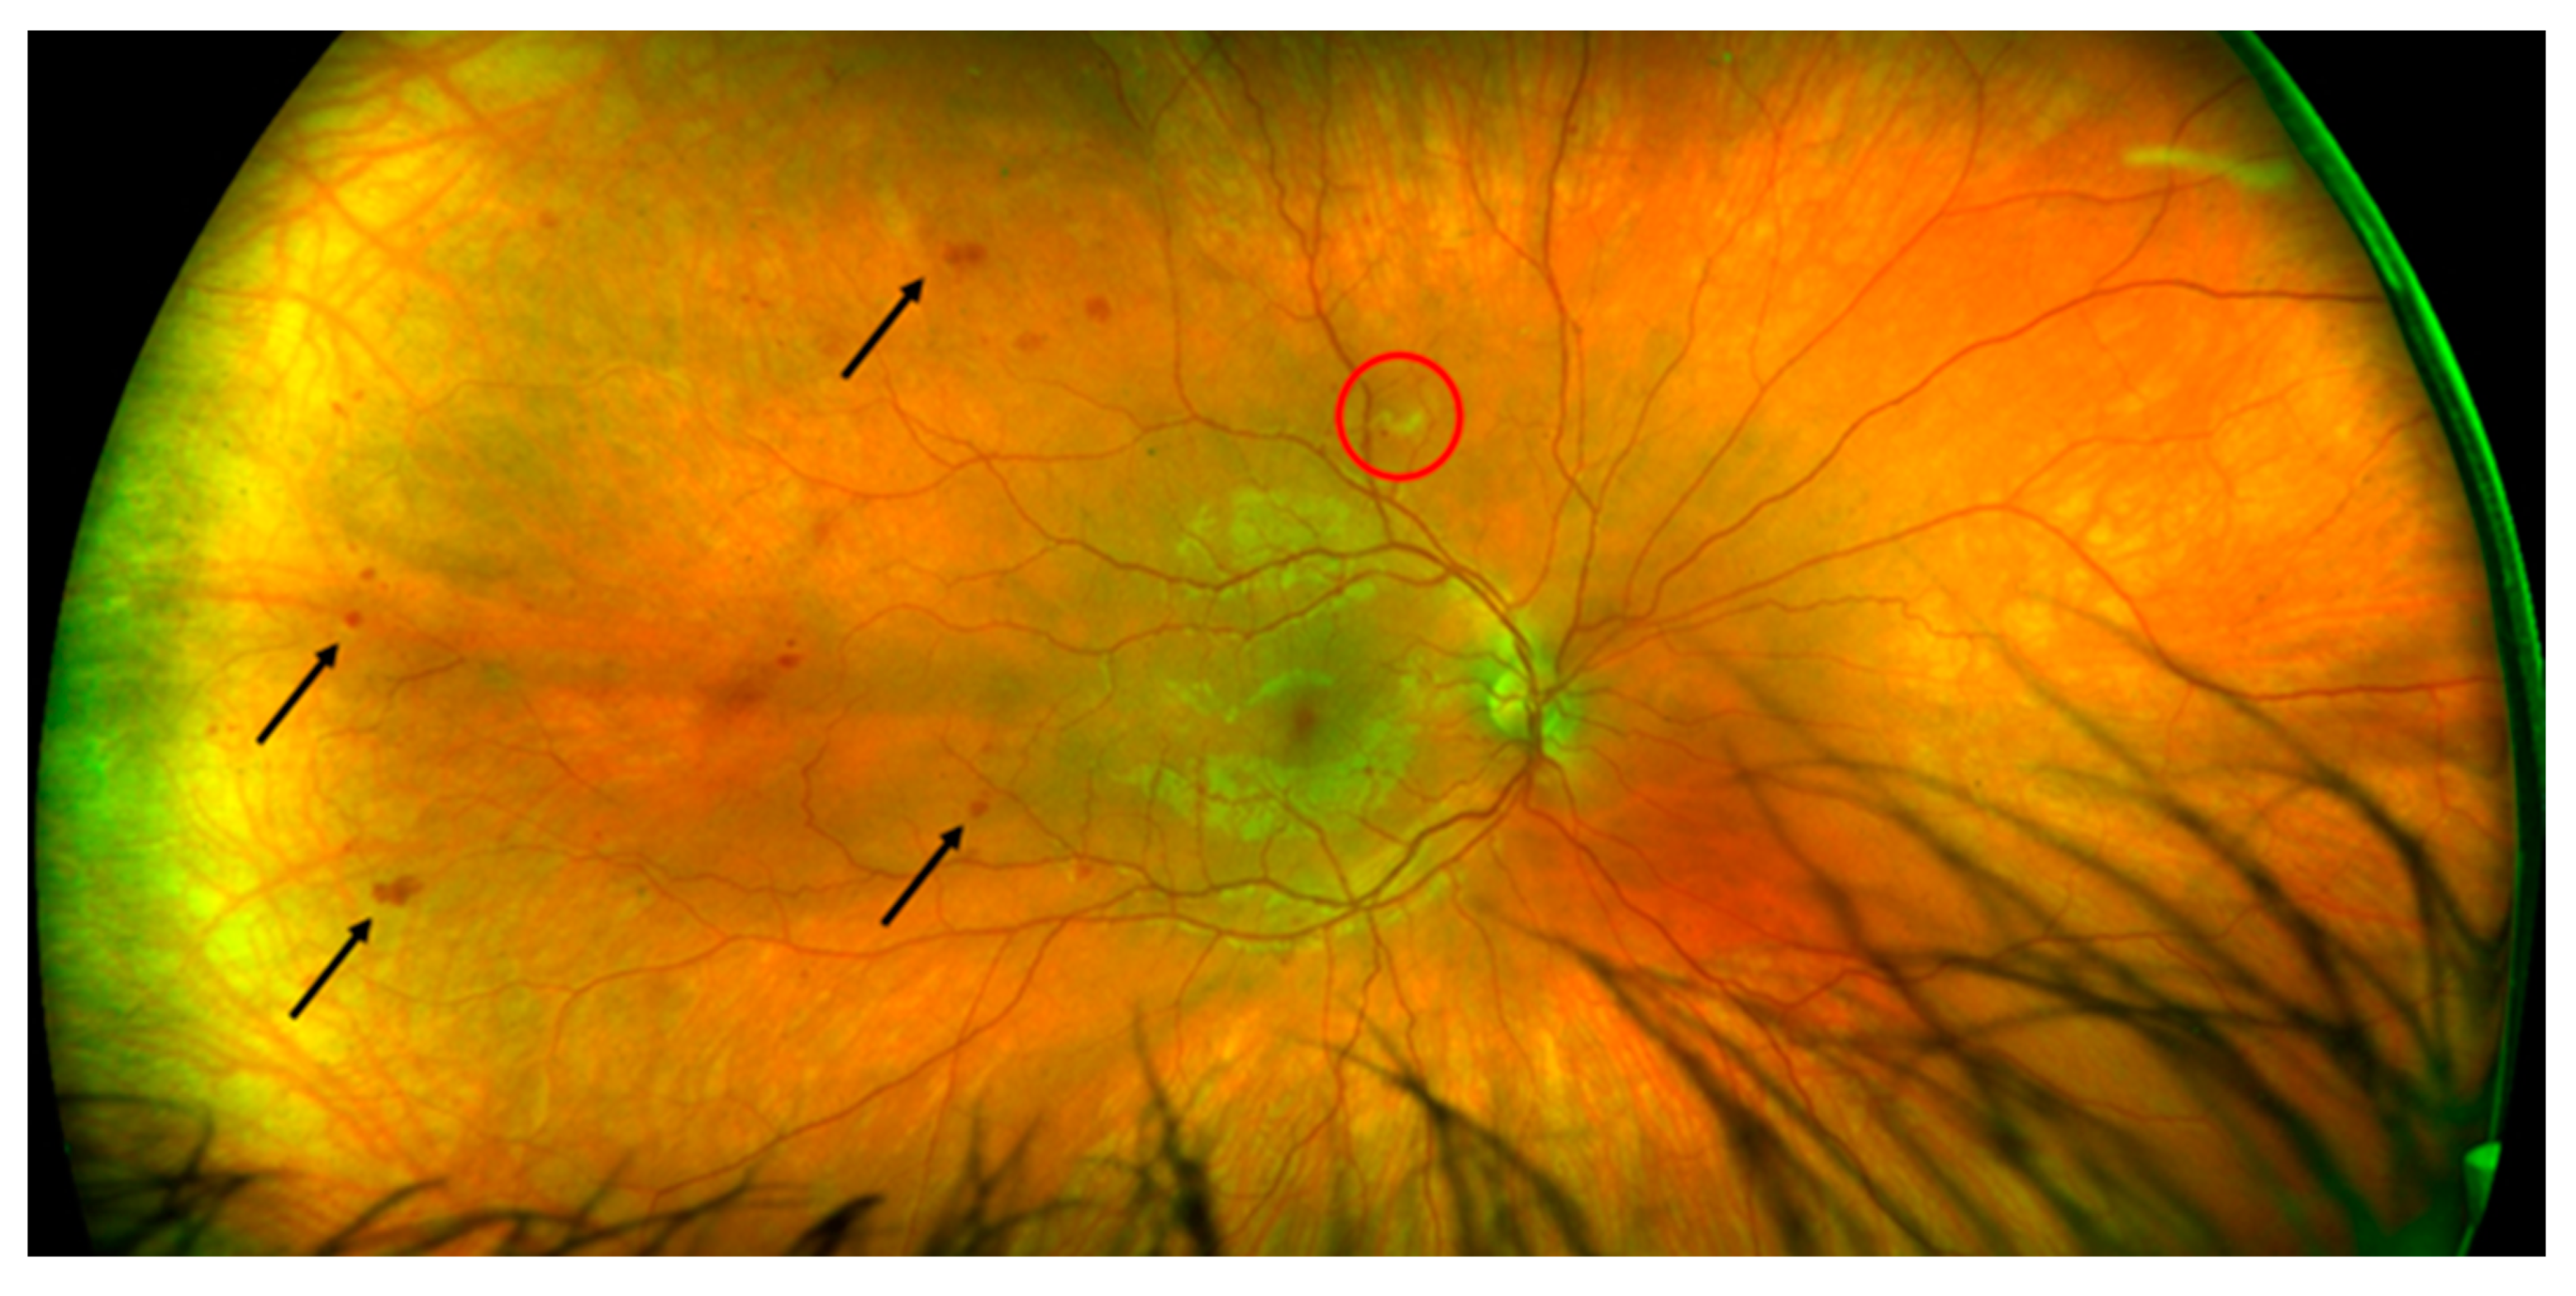

2. Case Description